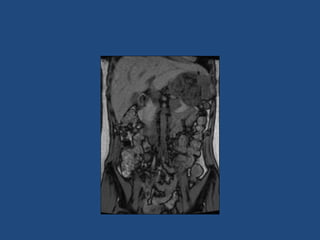

Imaging

•

>6cm high suspicion of malignancy

3-6cm repeat imaging in 3-6M

Delayed washout on contrast is suggestive

most are often inhomogeneous, irregular

margins

• Look for invasion of IVC

• Always do CAP and consider bone scan and

pet if in doubt

• Don’t ever biopsy (tumour spill)

Surgery

• Open adrenalectomy (ESMO clinical practice

guidelines suggests >10 adrenalectomies a year,

Dutch studies show improved survival if part of

cancer network)

• Laparoscopic can be considered if <8cm and not

obviously invasive

• Margin free resection only way to long term survival

(hence take kidney, IVC, liver as necessary)

• Consider resection of primary (even if

metastatic) as improved survival and

endocrinology

• Even seemingly complete resection initially:

50% chance of recurrence

• Surgery for recurrent disease good idea if

prolonged disease free interval, particularly if

chance of ‘complete’ resection

Imaging • • • • >6cm high suspicionof malignancy 3-6cm repeat imaging in 3-6M Delayed washout on contrast is suggestive most are often inhomogeneous, irregular margins • Look for invasion of IVC • Always do CAP and consider bone scan and pet if in doubt • Don’t ever biopsy (tumour spill)

Surgery • Open adrenalectomy(ESMO clinical practice guidelines suggests >10 adrenalectomies a year, Dutch studies show improved survival if part of cancer network) • Laparoscopic can be considered if <8cm and not obviously invasive • Margin free resection only way to long term survival (hence take kidney, IVC, liver as necessary)